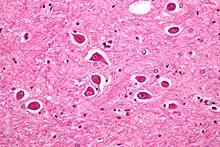

Micrograph of Alzheimer type II astrocytes, as may be seen in hepatic encephalopathy

There are various explanations why liver dysfunction or portosystemic shunting might lead to encephalopathy. In healthy subjects, nitrogen-containing compounds from the intestine, generated by gut bacteria from food, are transported by the portal vein to the liver, where 80–90% are metabolised through the urea cycle and/or excreted immediately. This process is impaired in all subtypes of hepatic encephalopathy, either because the hepatocytes (liver cells) are incapable of metabolising the waste products or because portal venous blood bypasses the liver through collateral circulation or a medically constructed shunt. Nitrogenous waste products accumulate in the systemic circulation (hence the older term "portosystemic encephalopathy"). The most important waste product is ammonia (NH3). This small molecule crosses the blood–brain barrier and is absorbed and metabolised by the astrocytes, a population of cells in the brain that constitutes 30% of the cerebral cortex. Astrocytes use ammonia when synthesising glutamine from glutamate. The increased levels of glutamine lead to an increase in osmotic pressure in the astrocytes, which become swollen. There is increased activity of the inhibitory γ-aminobutyric acid (GABA) system and the energy supply to other brain cells is decreased. This can be thought of as an example of brain edema of the "cytotoxic" type.[13]